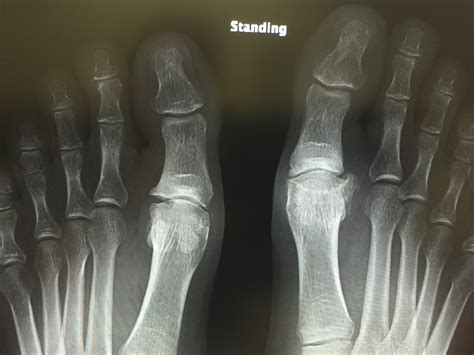

Minimally Invasive Hallux Rigidus Osteotomy | David Redfern Surgery